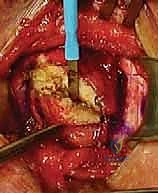

الخطوة 3: استئصال الجزء التالف من الترقوة (Resection)

باستخدام منشار جراحي دقيق للغاية، يتم استئصال الجزء الداخلي من عظم الترقوة (عادة ما بين 1 إلى 1.5 سنتيمتر). إزالة هذا الجزء يقضي تماماً على احتكاك العظام الذي يسبب الألم في حالات الخشونة، ويخلق مساحة لإعادة بناء المفصل في حالات الخلع.